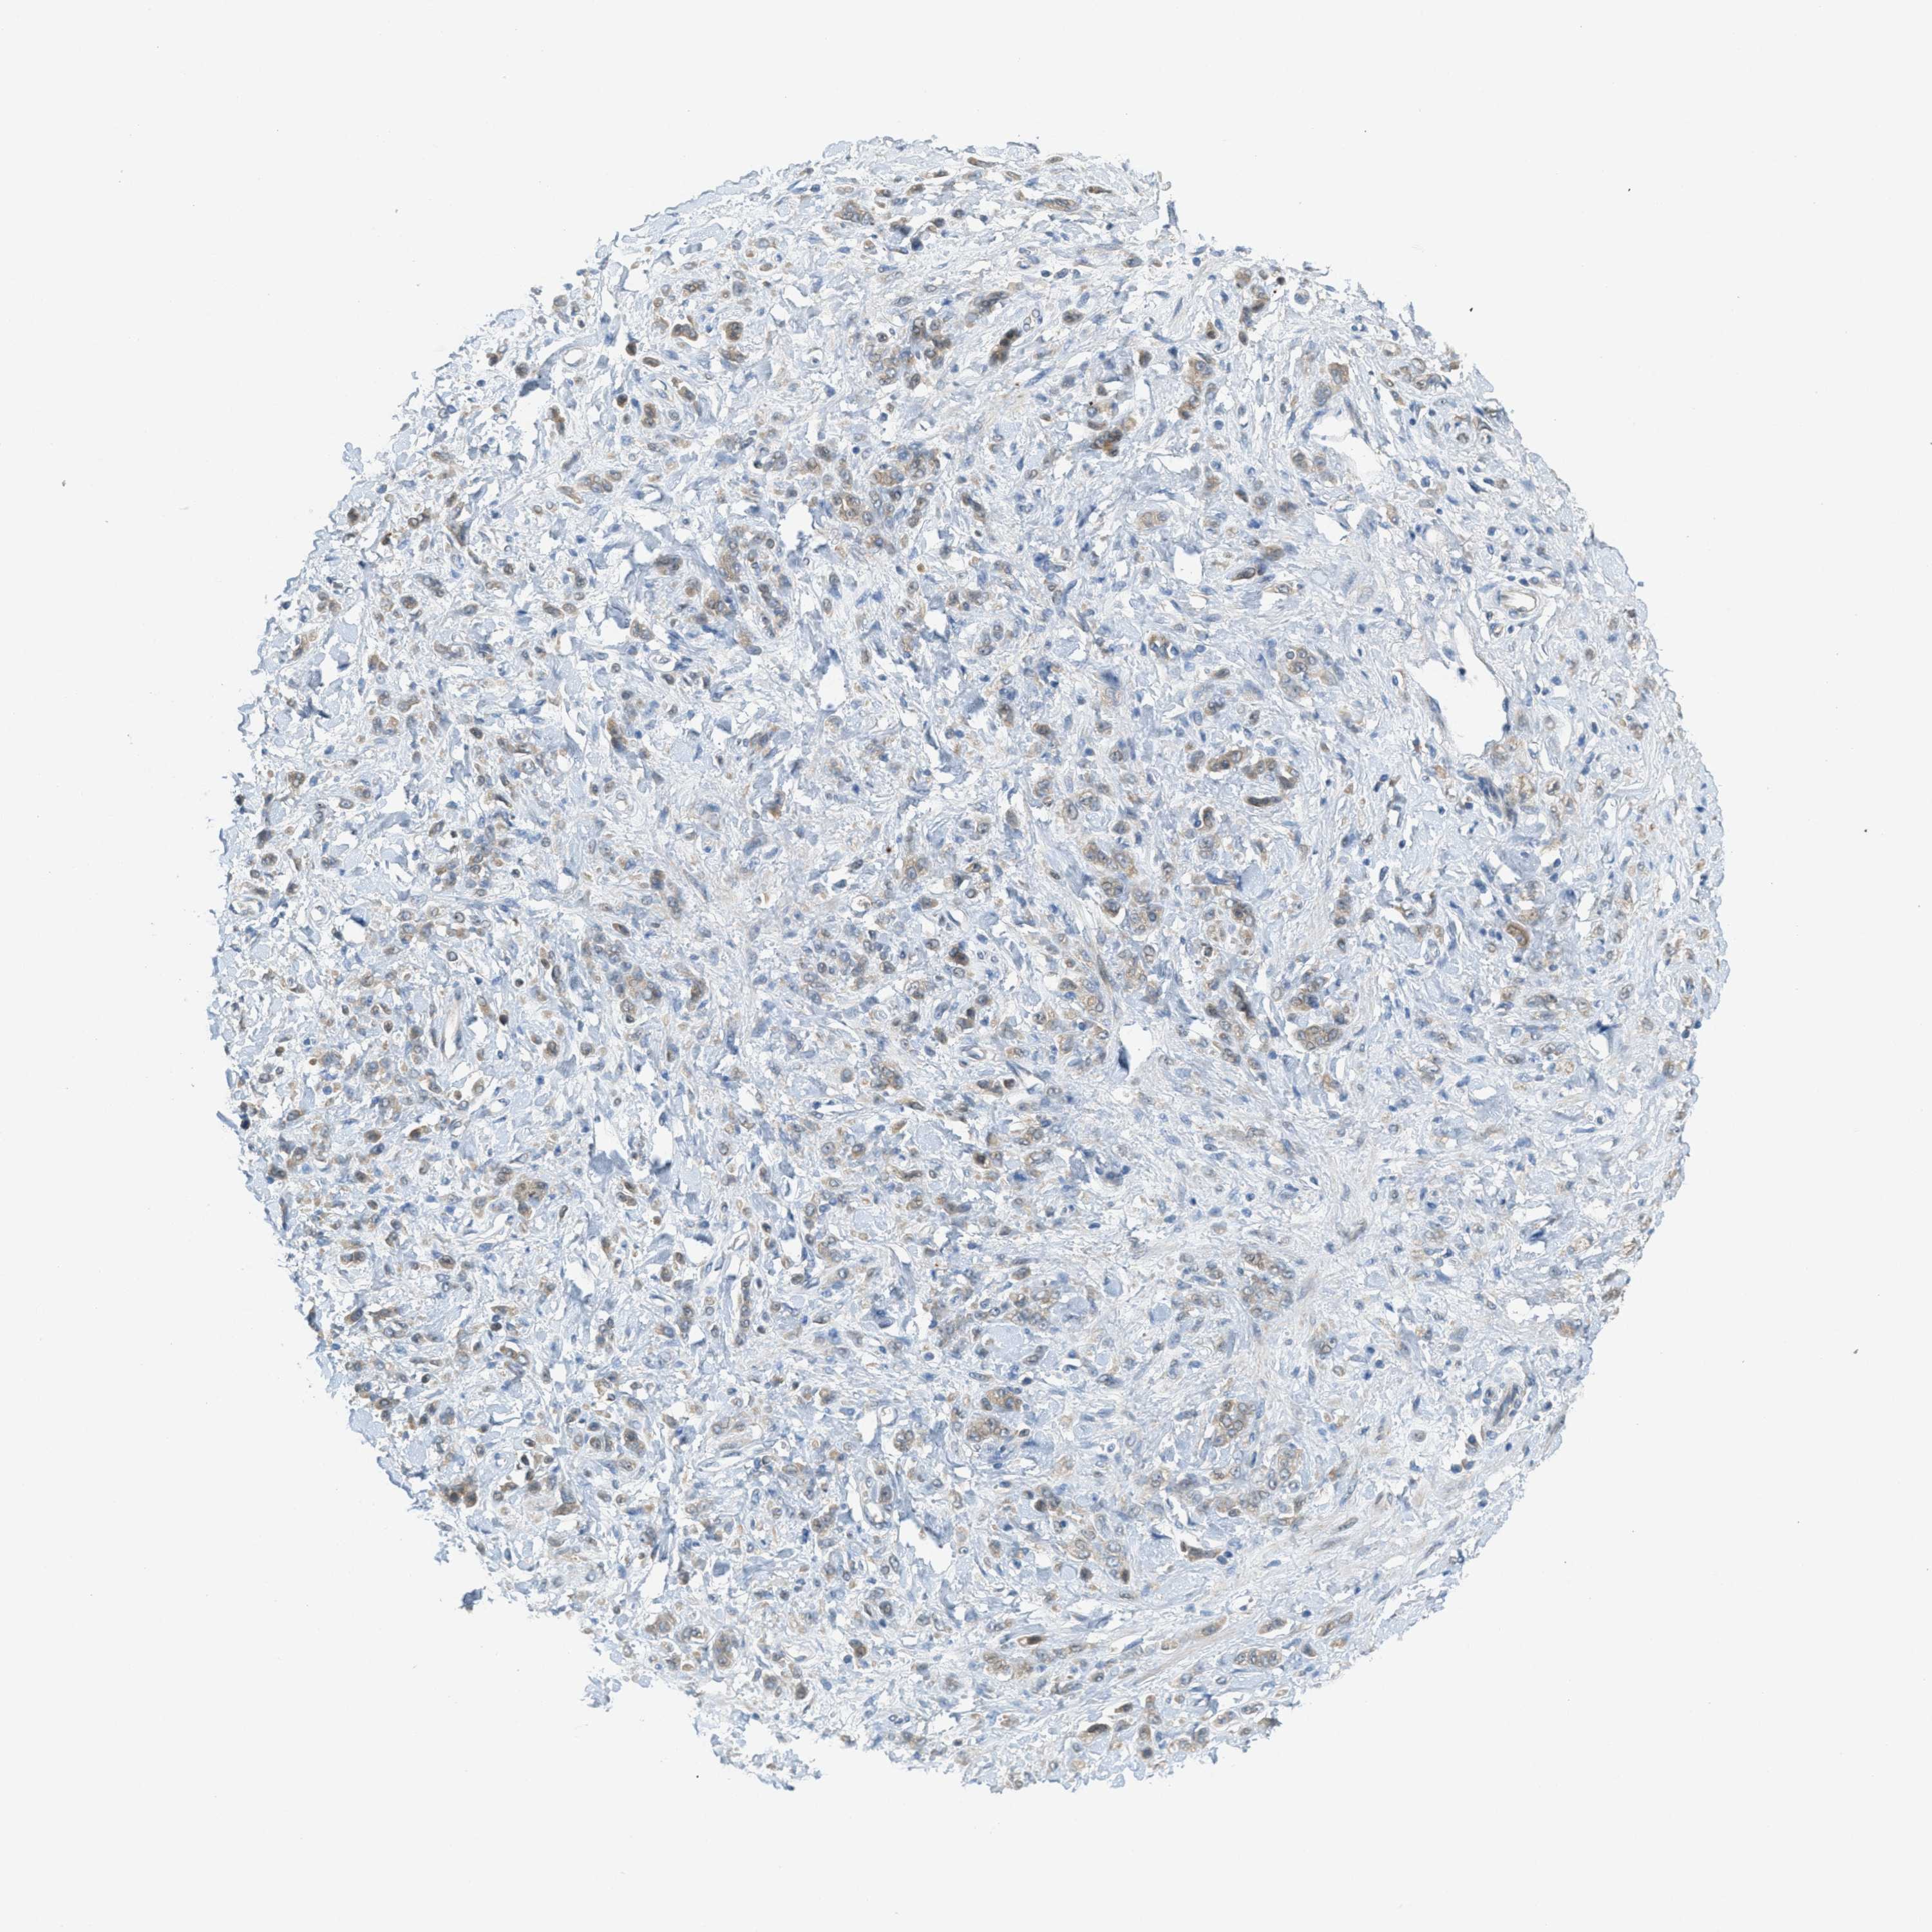

STOMACH CANCER - Protein expressioni

A mouse-over function shows sample information and annotation data. Click on an image to view it in a full screen mode. Samples can be filtered based on level of antibody staining by selecting one or several of the following categories: high, medium, low and not detected. The assay and annotation is described here.

Note that samples used for immunohistochemistry by the Human Protein Atlas do not correspond to samples in the TCGA dataset.

Antibody stainingi

Antibody staining in the annotated cell types in the current human tissue is reported as not detected, low, medium, or high, based on conventional immunohistochemistry profiling in selected tissues. This score is based on the combination of the staining intensity and fraction of stained cells.

Each image is clickable and will lead to virtual microscopy that enables deeper exploration of all samples and also displays staining intensity scores, fraction scores and subcellular localization as well as patient and tissue information for each sample.

Antibody HPA018002

Antibody HPA024071

Antibody CAB013470

Staining

High

Medium

Low

Not detected

Intensity

Strong

Moderate

Weak

Negative

Quantity

>75%

75%-25%

<25%

None

Location

Nuclear

Cytoplasmic/membranous

Cytoplasmic/membranous,nuclear

Adenocarcinoma, NOS

Adenocarcinoma, High grade